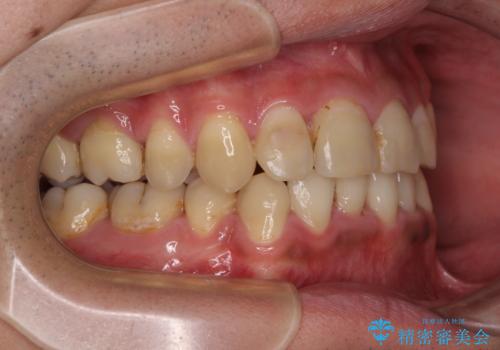

重なって磨きにくい上下の前歯 ワイヤー装置での抜歯矯正

- 前歯のデコボコを改善したいと来院された患者様です。

口元の突出感はないものの、上顎前歯のデコボコが著しかったため、上下顎左右小臼歯4本を抜歯することとしました。

第二小臼歯抜歯の矯正治療は、治療期間が長引くことが多いですが、動きが非常に良く、予定の治療期間で終えることができました。

上下の正中も思っていた以上に良い位置に改善されました。